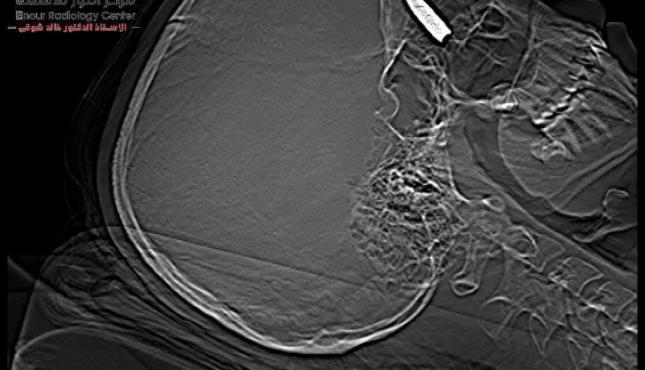

وكانت الشابة الفلسطينية قد تعرضت لإصابة بالغة نتيجة إصابتها بطلقة نارية اخترقت جمجمتها واستقرت خلف العين في منطقة حساسة، حيث تم إطلاقها من طائرة "كواد كابتر" خلال النزوح الذي تعرضت له في منطقة النصيرات.

ووصف الأطباء المصريون، العملية بأنها "بالغة التعقيد، حيث كان الطلق الناري قد استقر في منطقة حساسة داخل الجمجمة، مما كان يشكل تهديداً كبيراً على حياة المريضة".